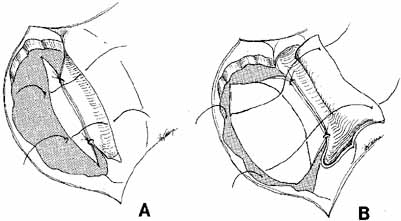

at the medial canthus.  Fig. 44 A. Silastic intubation is required after excision of scars in the area of

the common internal punctum and for moderate degrees of canaliculostenosis

or obstruction. The probes are placed through the upper and lower

canaliculi and through the common internal punctum. Any scar tissue

over this area is excised. B. The Silastic is brought down through the dacryocystorhinostomy (DCR) window

and cuffed as described earlier. This type of tubing with

a cuff will suffice as a stent in these instances, and will maintain

separation of the anterior and posterior mucosal flaps. Use of this

tubing eliminates the need for a catheter or for packing to act as a

stent. Fig. 44 A. Silastic intubation is required after excision of scars in the area of

the common internal punctum and for moderate degrees of canaliculostenosis

or obstruction. The probes are placed through the upper and lower

canaliculi and through the common internal punctum. Any scar tissue

over this area is excised. B. The Silastic is brought down through the dacryocystorhinostomy (DCR) window

and cuffed as described earlier. This type of tubing with

a cuff will suffice as a stent in these instances, and will maintain

separation of the anterior and posterior mucosal flaps. Use of this

tubing eliminates the need for a catheter or for packing to act as a

stent.